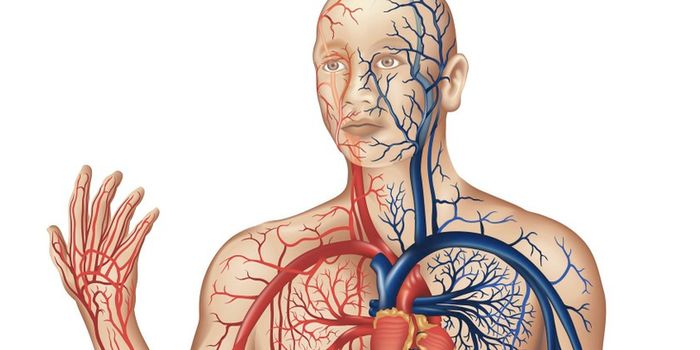

Cardiology is an ever-evolving branch of medicine concerned with disease and disorders of the heart. Cardiology trending provides articles and resources to keep you informed on risk factors, causes and prevention of heart disease, evidence-based research and advances in treatment.